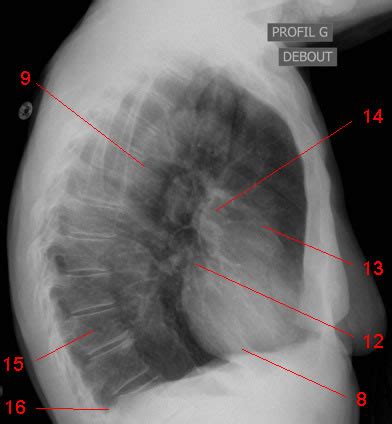

Le médiastin, la région centrale du thorax située entre les deux poumons, abrite des structures vitales telles que le cœur, l'aorte, la trachée, l'œsophage et les ganglions lymphatiques. Les contours médiastinaux, visibles sur les radiographies de thorax, fournissent des informations précieuses sur l'état de ces organes. À droite, l'arc supérieur correspond au tronc veineux brachio-céphalique droit, l'arc moyen à la veine cave supérieure, et l'arc inférieur à l'atrium droit et, dans une moindre mesure, à la veine cave inférieure. Le hile pulmonaire gauche est physiologiquement situé légèrement plus haut que le hile droit.

L'interprétation d'une radiographie thoracique implique l'analyse des différents éléments anatomiques, y compris les structures médiastinales et les contours cardiaques. Le signe de la silhouette est un outil précieux pour localiser une opacité en déterminant si elle est en contact avec une structure de densité similaire, rendant leurs contours indistincts.